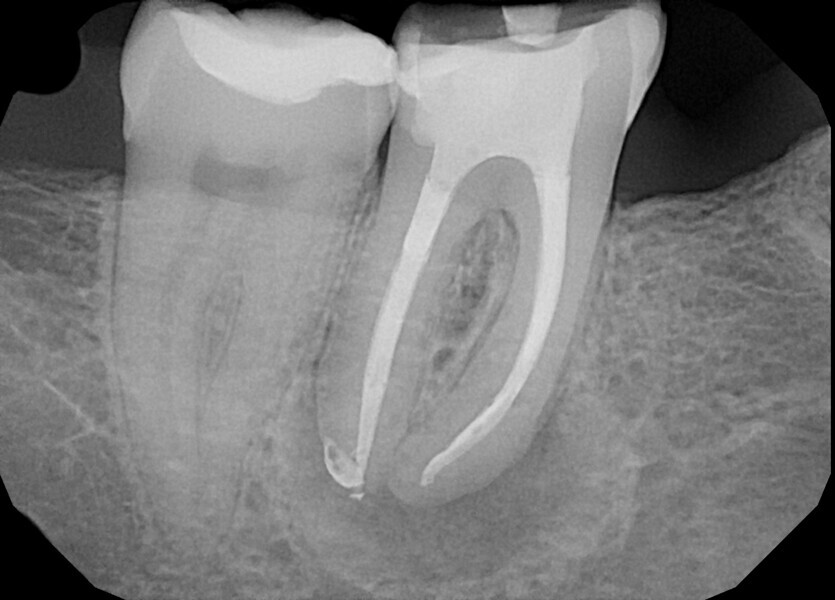

Instrumentation was then performed with the R25 RECIPROC blue up to the level of the split, and the split was prepared with the 12.5/0.04 R-PILOT (VDW; Fig. 18). The final irrigation protocol was performed with copious amount of fluids (sodium hypochlorite and citric acid with a final rinse of distilled water; Fig. 19). Obturation was performed with the piston technique, and the restoration was done with composite material (Fig. 20). The patient was referred to the prosthodontist for final restoration. On the final CBCT scan, it was clearly visible that the piston technique had helped to obturate the deep split in the apical area (Fig. 21).

From this point of view, a novel approach of placing a tricalcium silicate-based sealer was a promising idea. The sealer was placed in the previously described manner. The premixed sealer in the plastic syringe (Meta Biomed) was placed in the mesiobuccal canal and the syringe depressed until it filled the mesiolingual canal. The distal canal was filled separately. In each canal, pistons from the previously heated gutta-percha extruder were placed and the warm gutta-percha was slightly compacted with stainless-steel hand condensers. A periapical radiograph was taken to evaluate the quality of the obturation. The bioceramic sealer was slightly extruded through the resorbed apex into the periapical area (Fig. 36). After the obturation, the chamber and orifices were cleaned (Fig. 37). A resin core with fibre posts was placed, and the temporary pink material was removed. The patient was referred to the prosthodontist for final restoration.

The recall appointment was performed after three years. The periapical radiograph and CBCT scan revealed healing of the periapical tissue and no resorption of the bioceramic sealer (Fig. 38). The tooth remained asymptomatic.